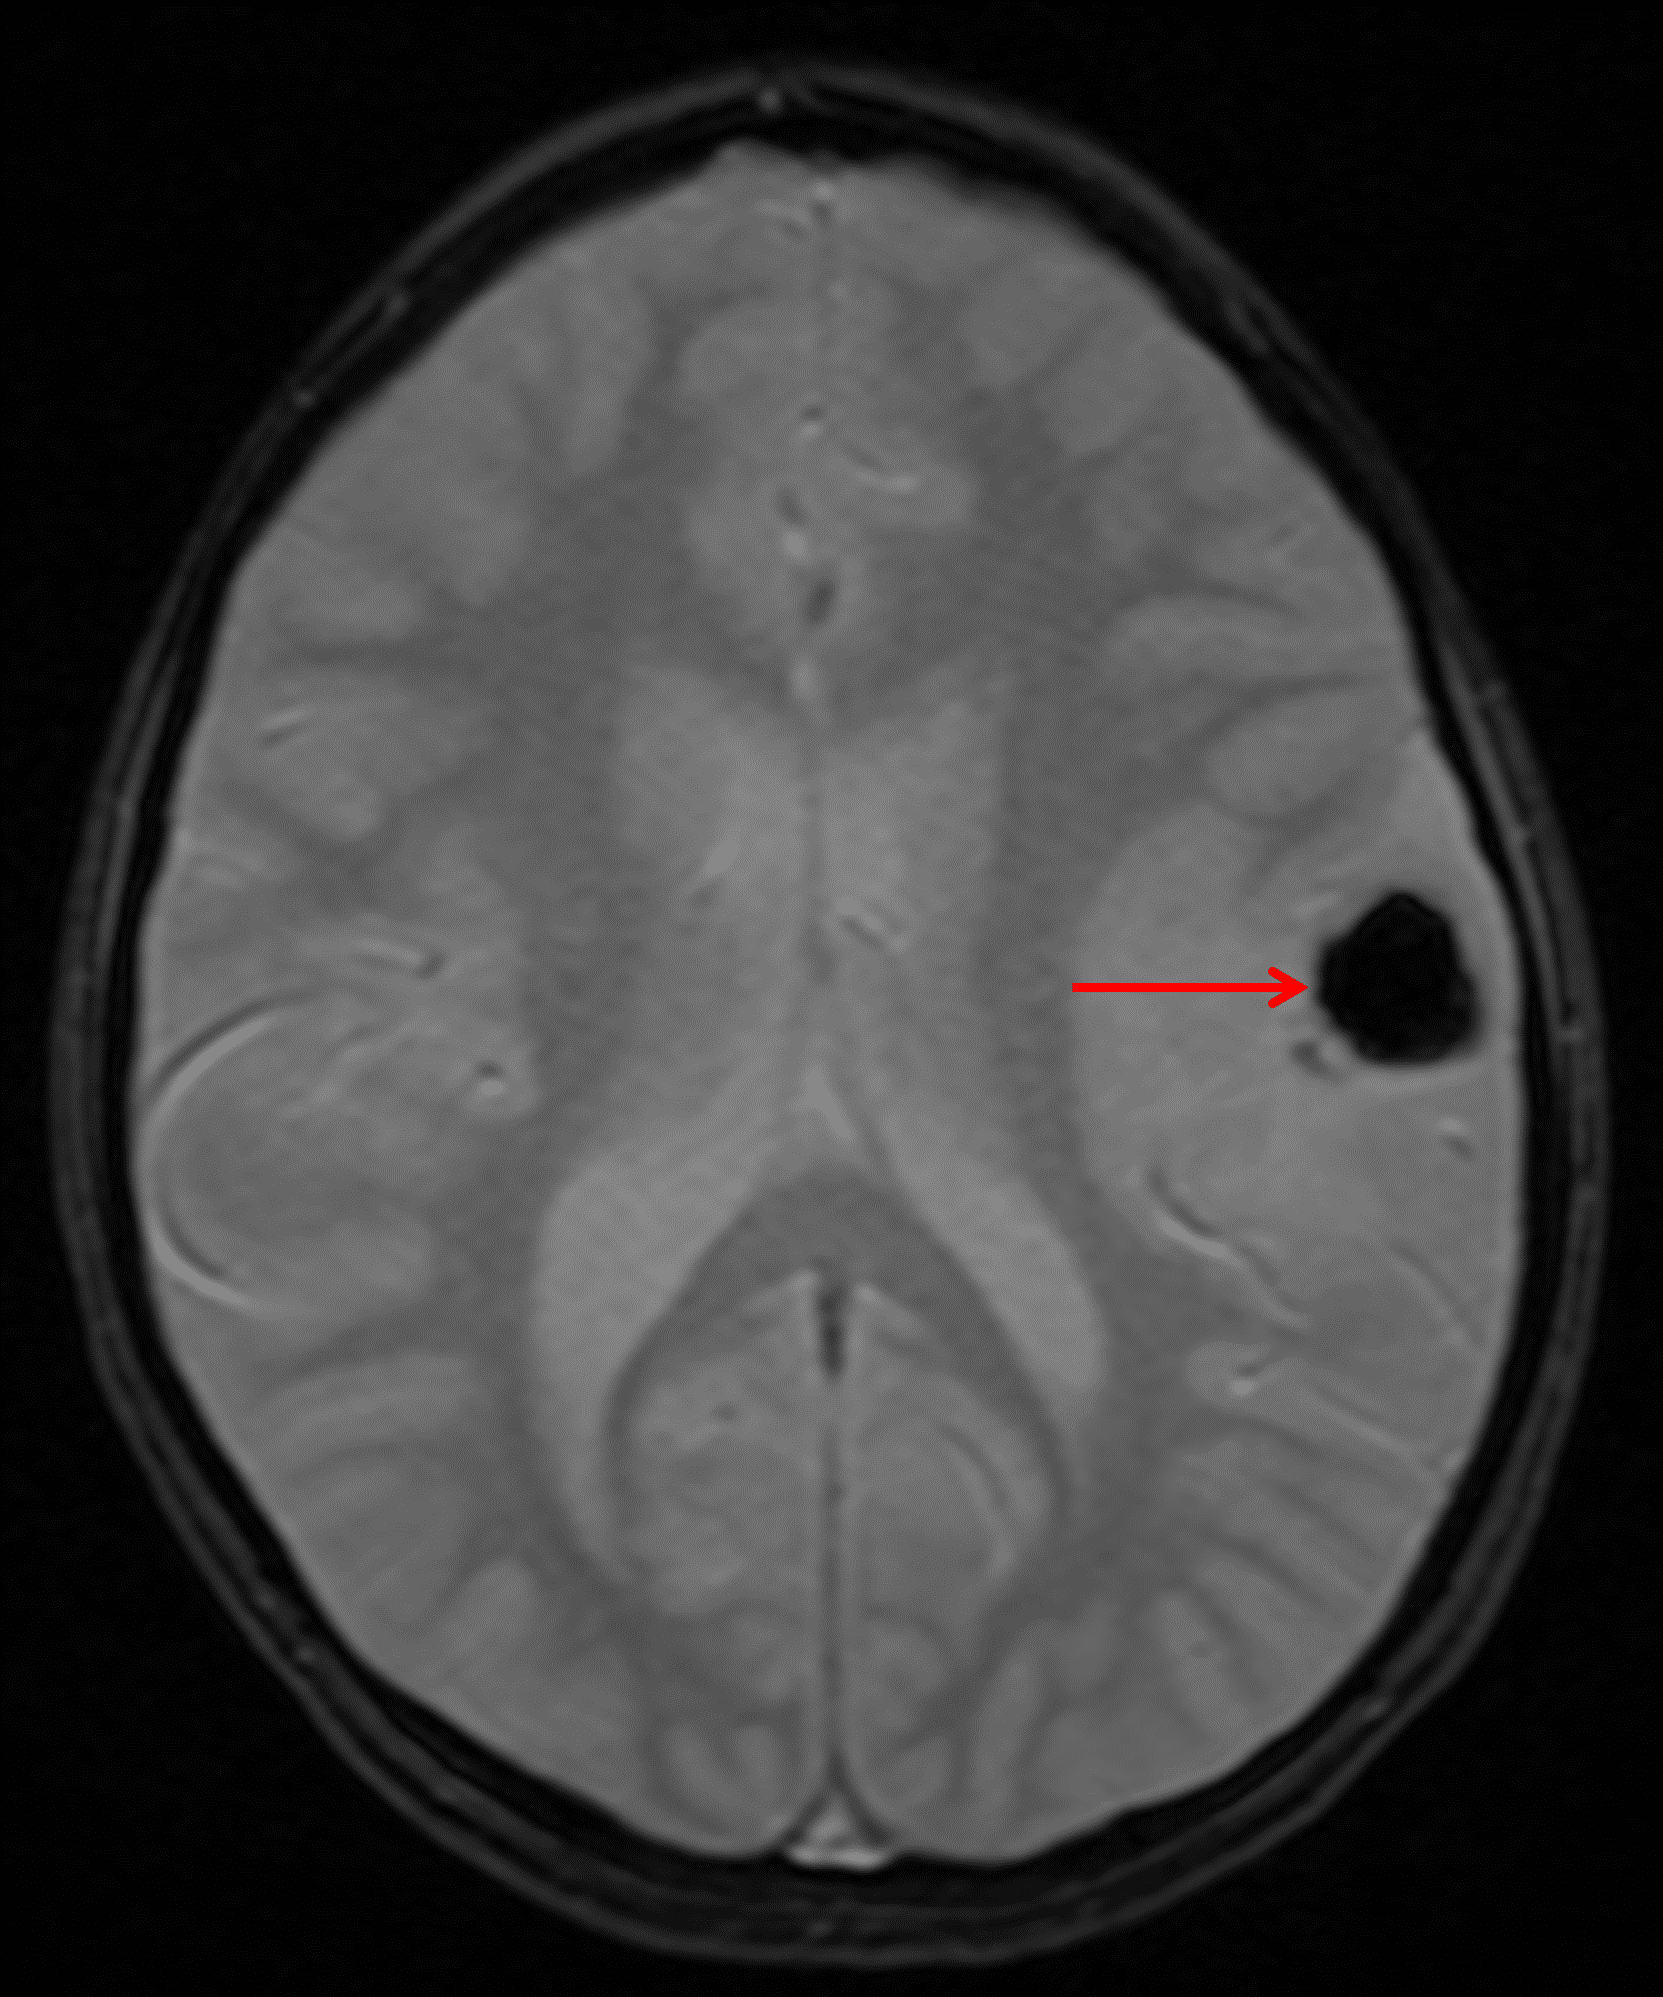

- Large rounded internal area of susceptibility artifact consistent with calcification

Annotated Images & Illustrations

Rounded area of susceptibility artifact within the tumor (red arrow) corresponding to internal calcification.